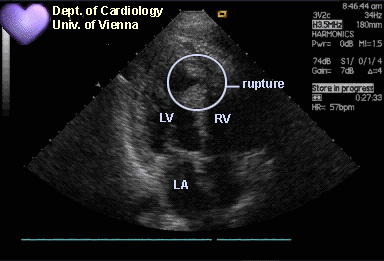

【"医"站到底】26:主动脉瓣机械瓣置换术后发热,您答对了吗?

2份典型病例,带你寻找主动脉夹层的真凶!